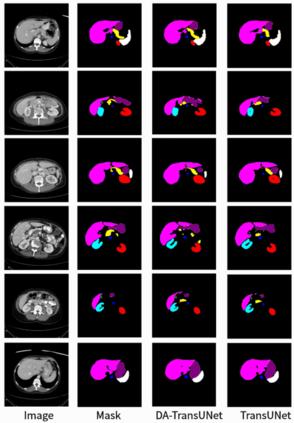

Accurate medical image segmentation is critical for disease quantification and treatment evaluation. While traditional Unet architectures and their transformer-integrated variants excel in automated segmentation tasks. However, they lack the ability to harness the intrinsic position and channel features of image. Existing models also struggle with parameter efficiency and computational complexity, often due to the extensive use of Transformers. To address these issues, this study proposes a novel deep medical image segmentation framework, called DA-TransUNet, aiming to integrate the Transformer and dual attention block(DA-Block) into the traditional U-shaped architecture. Unlike earlier transformer-based U-net models, DA-TransUNet utilizes Transformers and DA-Block to integrate not only global and local features, but also image-specific positional and channel features, improving the performance of medical image segmentation. By incorporating a DA-Block at the embedding layer and within each skip connection layer, we substantially enhance feature extraction capabilities and improve the efficiency of the encoder-decoder structure. DA-TransUNet demonstrates superior performance in medical image segmentation tasks, consistently outperforming state-of-the-art techniques across multiple datasets. In summary, DA-TransUNet offers a significant advancement in medical image segmentation, providing an effective and powerful alternative to existing techniques. Our architecture stands out for its ability to improve segmentation accuracy, thereby advancing the field of automated medical image diagnostics. The codes and parameters of our model will be publicly available at https://github.com/SUN-1024/DA-TransUnet.